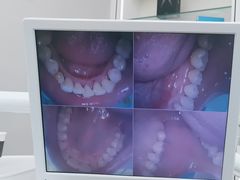

• 牙博士口腔品牌连锁(杨浦店)

• -牙博士口腔品牌连锁(杨浦店)